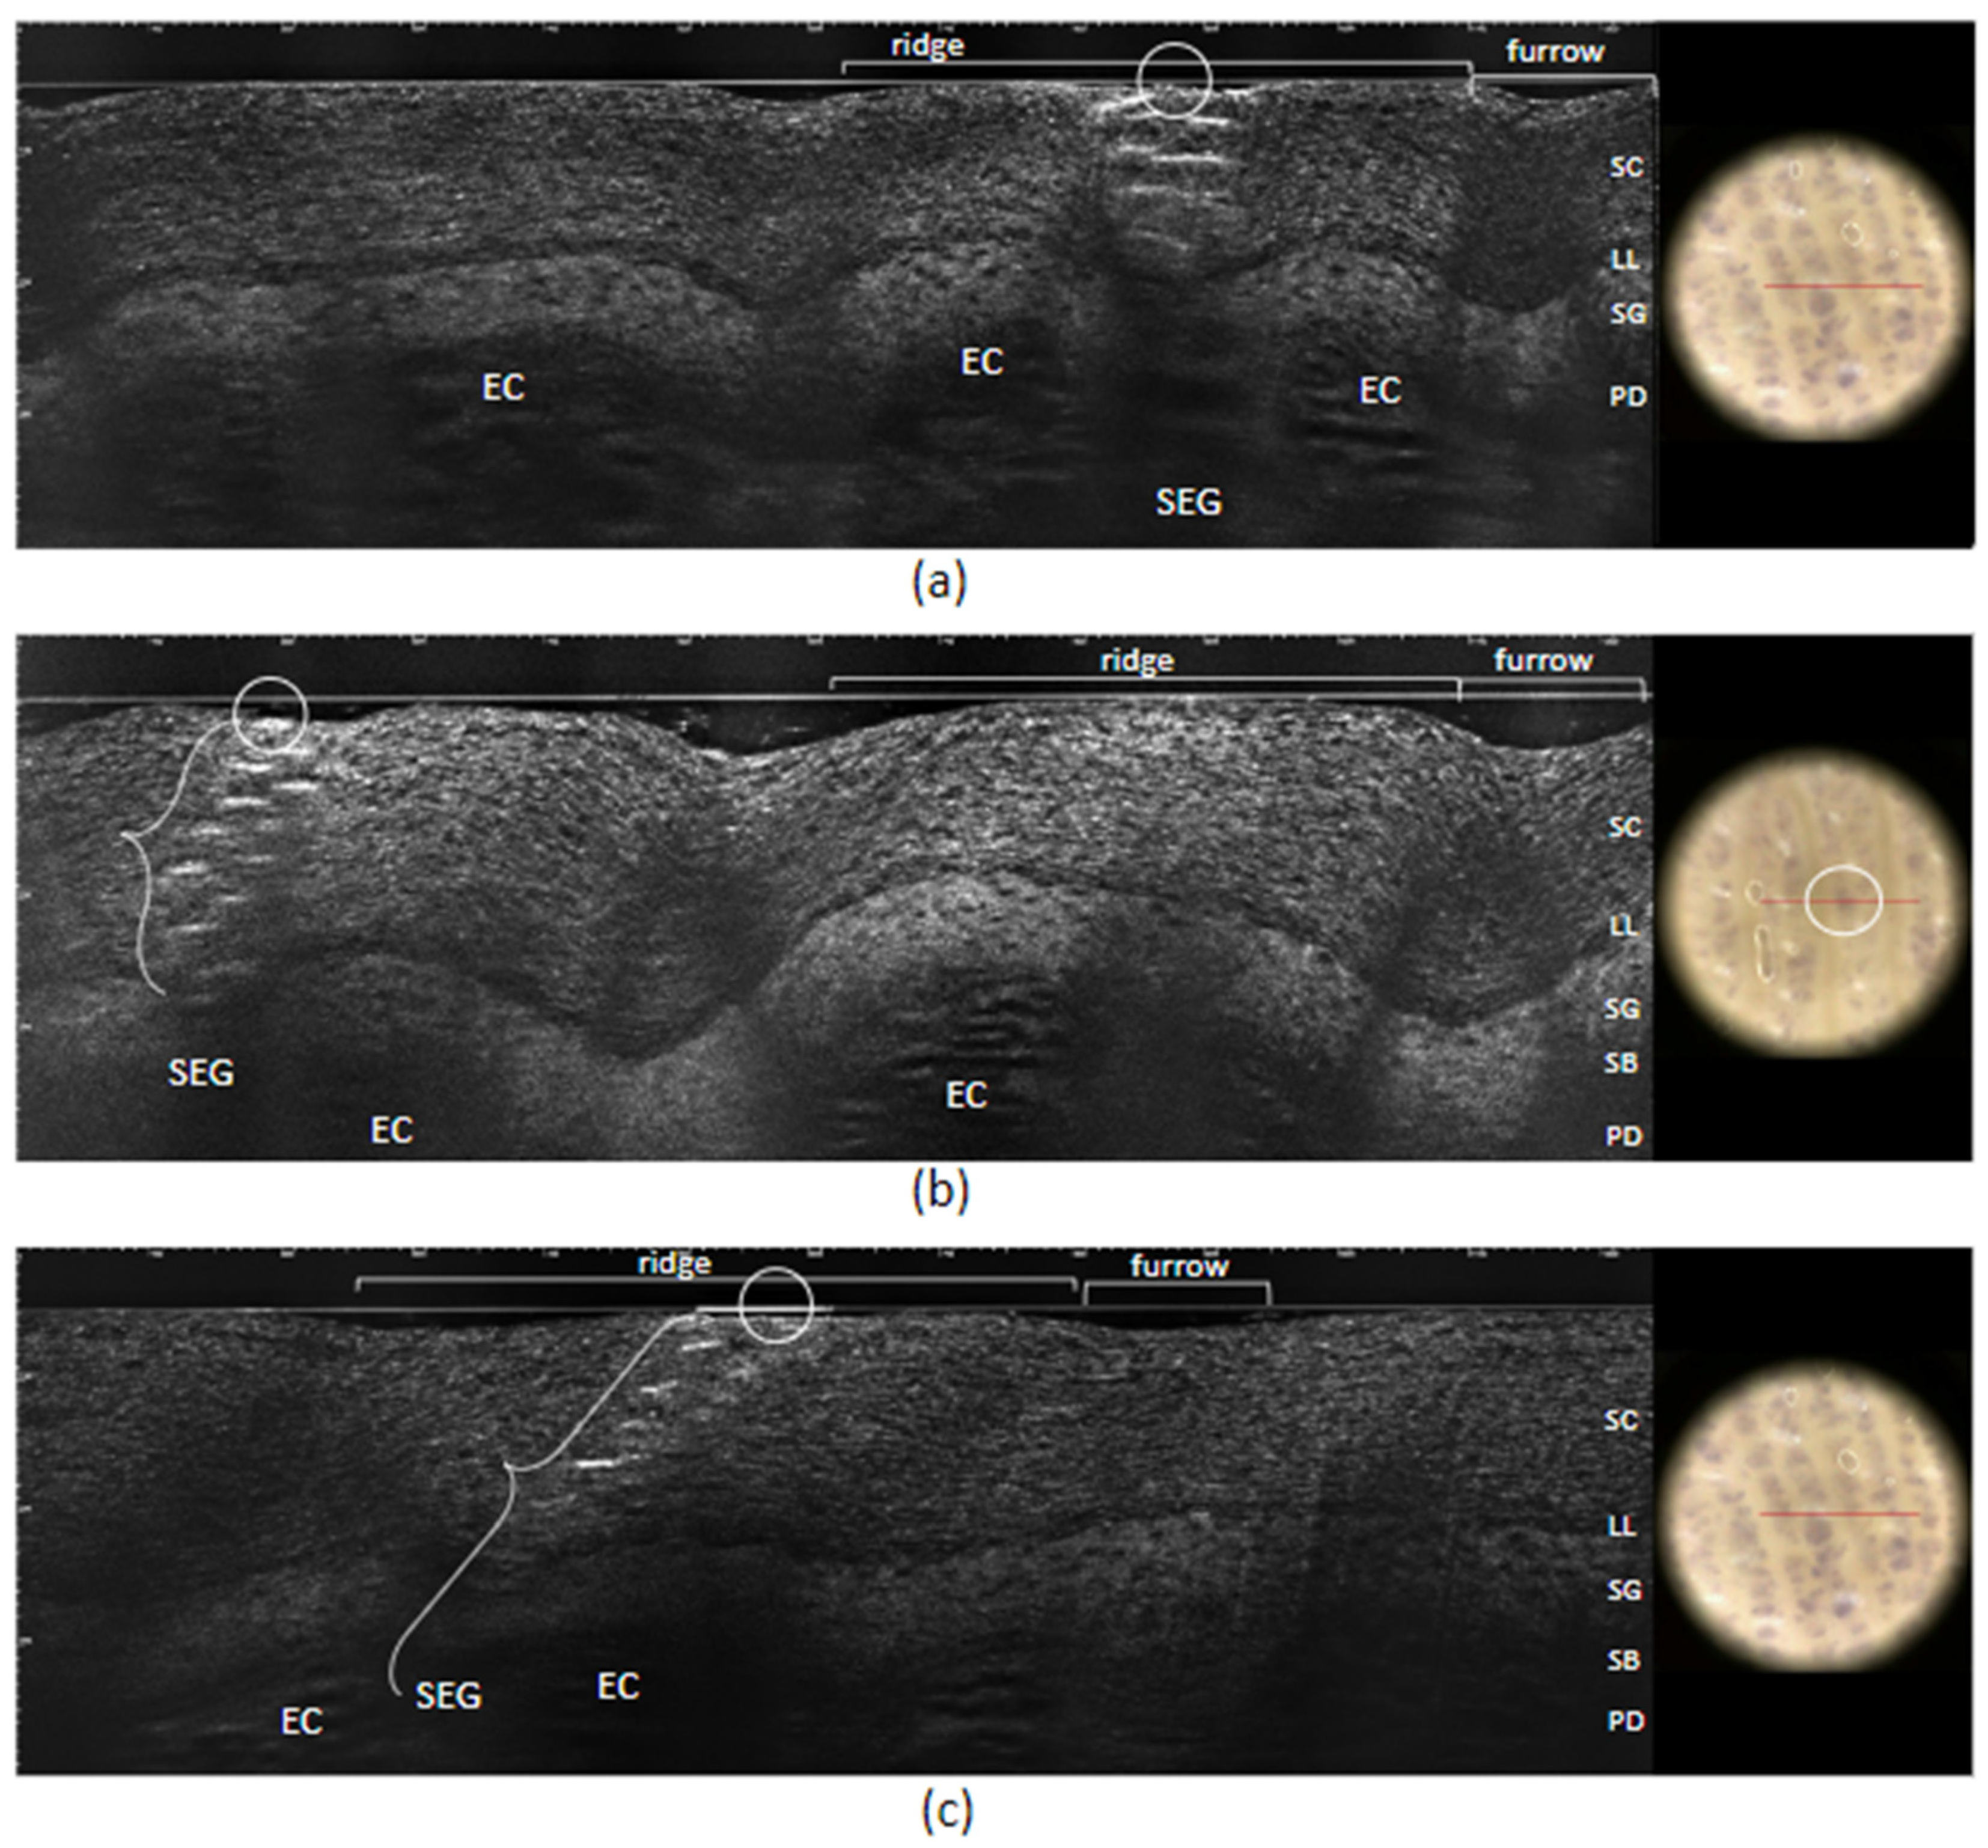

2. Case Report

3. Discussion